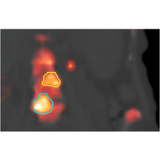

MIM SurePlan MRT performs voxel-based absorbed dose calculation using the patient's own anatomy. MIM SurePlan MRT calculates dose using the voxel s-value (VSV) schema in MIRD Pamphlet No. 17 and provides dose maps and DVH curves for analysis. Tools for Lu-177 and I-131 FDA approved therapies are available for clinical use and tools for other radionuclide therapies are available for research use.